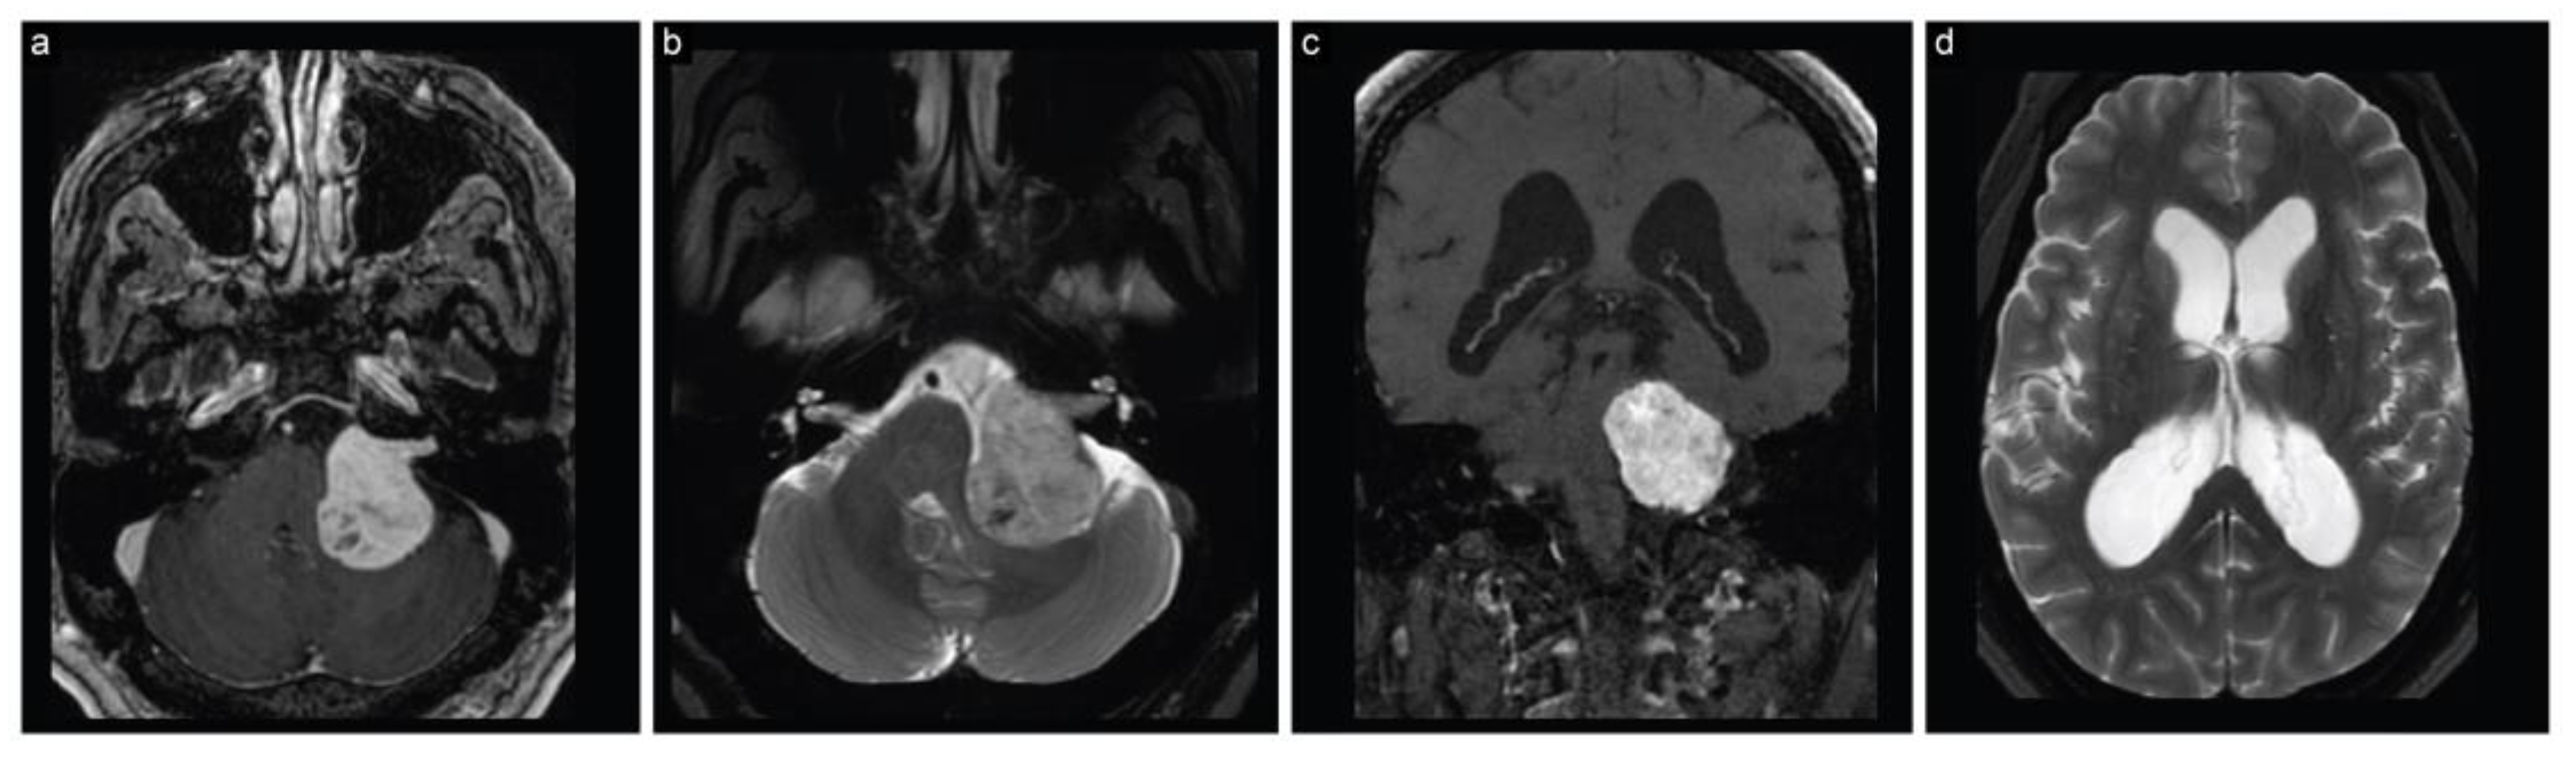

The patient immediately had a cranial MRI that displayed a sizeable (4 cm × 3.5 cm × 3.3 cm) left CPA lesion, consistent with a vestibular schwannoma (Figure 1). The lesion caused marked compression on the brainstem and fourth ventricle, resulting in hydrocephalus.

Figure 1.

Case 1, preoperative neuroimaging. (a) Axial T1-weighted postcontrast, (b) axial T2-weighted, (c) coronal T1-weighted postcontrast, and (d) axial T2-weighted MRI scans show a large CPA lesion suggesting a vestibular schwannoma along with hydrocephalus.